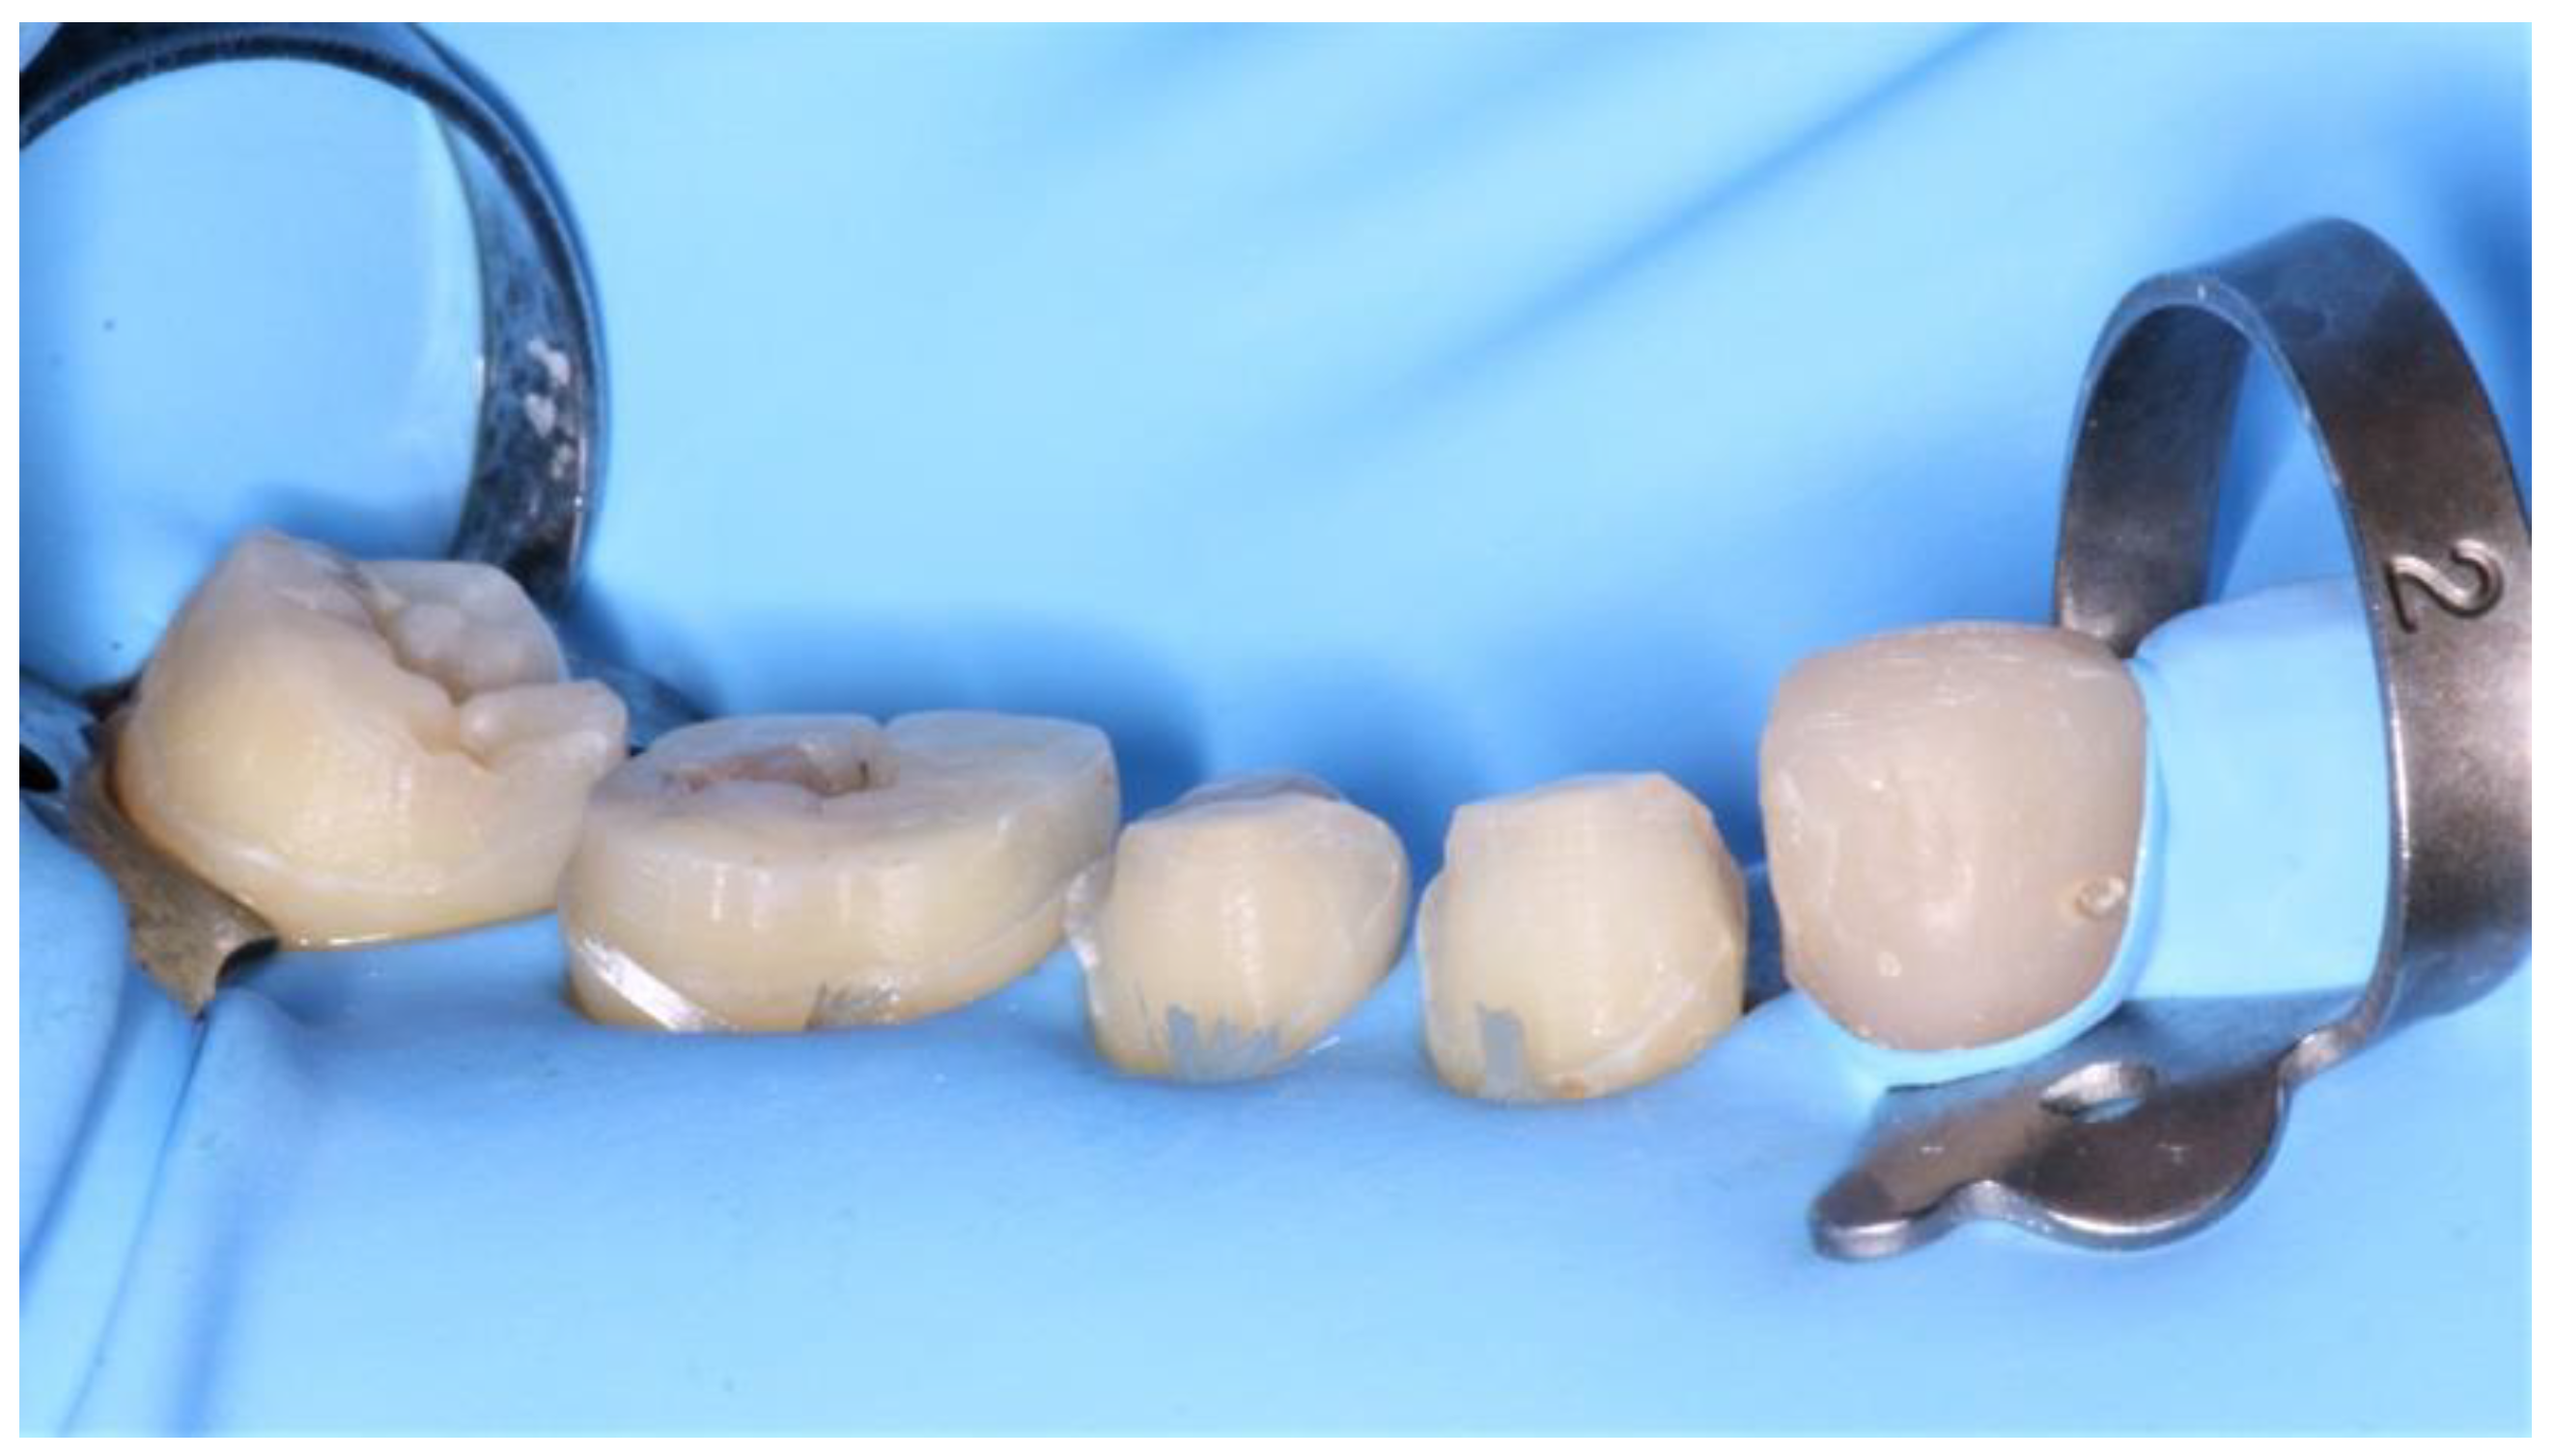

During the second clinical session, the temporary resin was applied, the teeth were thoroughly cleaned, and the fixed prosthetic components (Figure 11) were tried on.

Figure 11.

Fixed prosthetic elements traditionally glazed and polished.

Once validated, a rubber dam was installed (Figure 12) to allow optimal bonding according to the protocol described above (Figure 13).